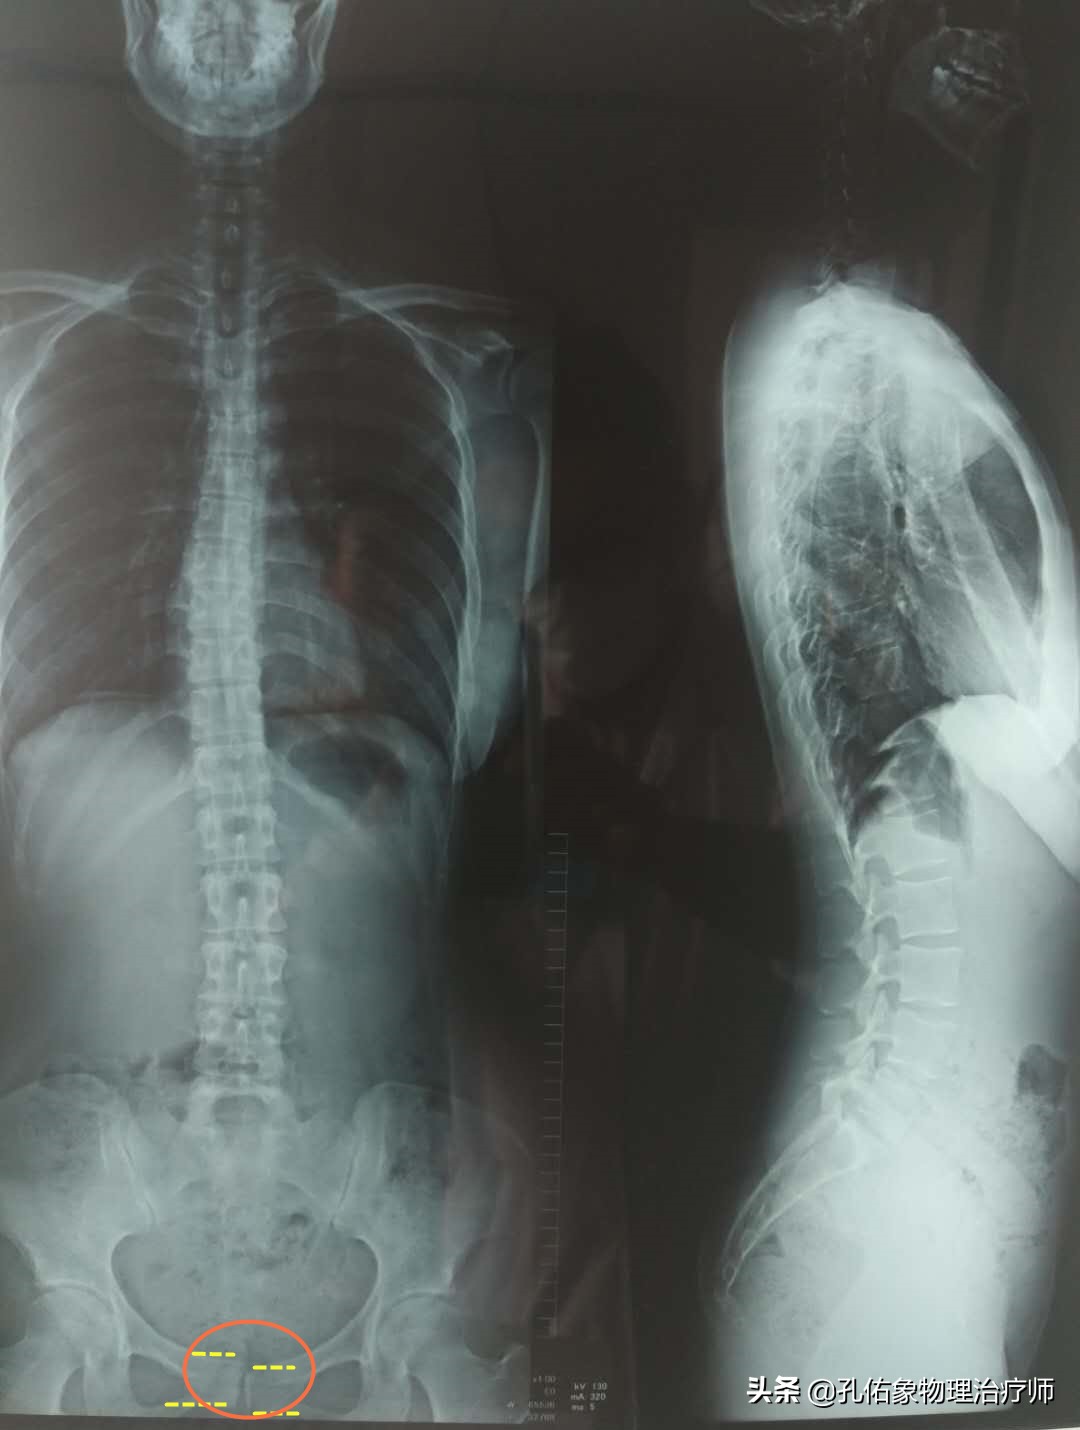

很多年轻女性,在怀孕期间,骨盆会随着激素和胎儿的变化而变化,或是在生产过程中,会阴区的撕裂伤等,都会导致耻骨联合的分离错位。如下图所示:

耻骨左右分离

耻骨上下移位

这样的错位,会在您不轻易的动作下产生大腿根部内侧缘的疼痛,一般会在产后一定时间内会自然愈合,不需要特殊的处理;若是一段时间没恢复的话,疼痛仍然存在,就需要前往医院,通过手法及骨盆运动等方式来修复。